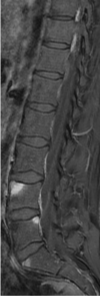

Imaging in ankylosing spondylitis: Sacro-iliitis on MRI

38

Spinal MRI in Ankylosing Spondylitis-Advantage over Xray? What is an MRI sign of AS on MRI?

MRI can detect spinal inflammation before X-rays changes develop In image we see “Shiny corners” sign at L4, L5 and S1